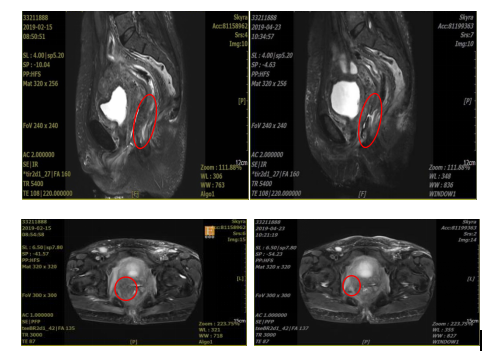

MRI:病变直径缩小1cm,肿瘤体积减少约50%

盆腔MRI提示:阴道肿瘤侵犯直肠